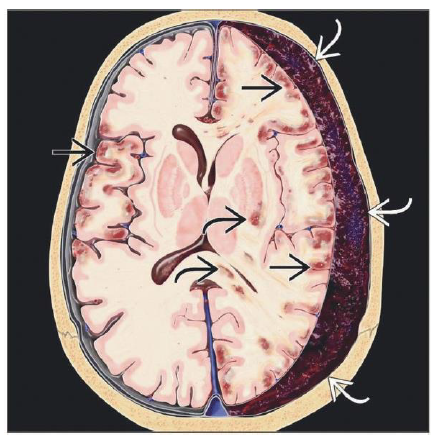

What is your dx?

Graphic depicts crescent-shaped acute SDH with contusions and “contre-coup” injuries , diffuse axonal injuries

What structures have been affected in this pt with SDH?

Acute SDH spreads over left hemisphere , along tentorium , into interhemispheric fissure but does not cross midline.